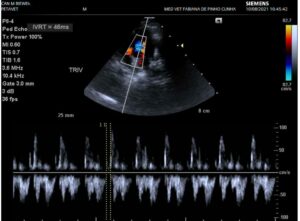

O exame ecocardiograma com doppler é um ultrassom do coração, onde a vet avalia o órgão internamente, seus vasos e o fluxo sanguíneo que entra e sai do coração.

Através de ângulos (chamados tecnicamente de “cortes”) feitos com o transdutor (aparelho de ultrassom que recebe aquele gelzinho geladinho na ponta), os átrios, ventrículos, paredes, artérias, veias e valvas são examinadas sob o aspecto anatômico e funcional.

As cores azuis e vermelhas revelam o fluxo de sangue (o que está entrando e o que está saindo, a direção, se está havendo escape, retorno, entre outros detalhes).

O som forte, que remete ao batimento cardíaco, é do fluxo dentro da artéria.